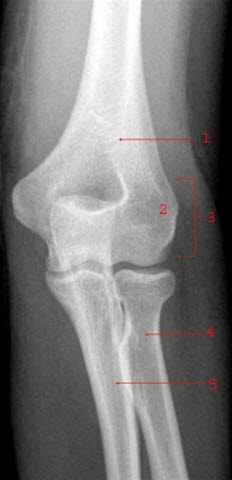

AlbueleddetDette er en tilstand som ikke har noe godt norsk navn. Innenfor medisinen har den derimot en rekke ulike engelske benevnelser: Pulled elbow, nursemaid's elbow, supermarket elbow, m.fl. Tilstanden ses vanligvis hos barn under 5 år og har en årlig forekomst på rundt 1%.

Hodet til spolebeinet (radius) dras nedover og delvis ut av ledd.